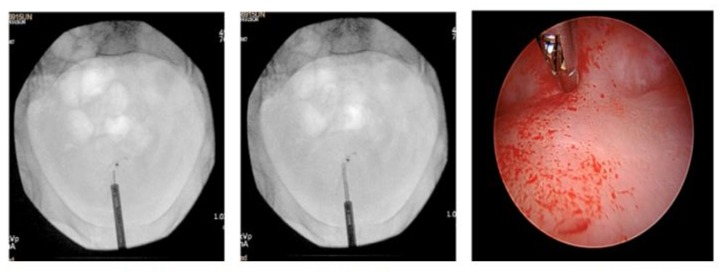

Next, we introduced the MyoSure Reach device into the cavity. Using the device’s tip, we palpated the posterior uterine wall where the IUD strings were seen prior to detachment. To precisely locate the IUD, portable X-ray imaging was performed with the MyoSure device in place to serve as a reference point.

We then systematically excised endometrial tissue at the radiographic site of the IUD, taking multiple X-ray images throughout the dissection to confirm the accurate location of the IUD in reference to the MyoSure instrument and to ensure precise dissection planes. Once a portion of the IUD was exposed, we carefully resected the surrounding tissue to liberate a significant part of the device. Hysteroscopic forceps were used to completely remove the IUD. It was found to be lying parallel to the uterine wall, requiring a larger area of exposure to achieve adequate traction for removal. Notably, we injected vasopressin into the myometrium with a hysteroscopic needle to decrease blood loss during dissection (Figures 1-5).

Figure 3: X-ray imaging guiding the initial dissection point of the MyoSure device along the posterior wall of the uterine cavity.

Figure 4: Hysteroscopic resection of the embedded IUD using the MyoSure device, following confirmation of its location with X-ray.